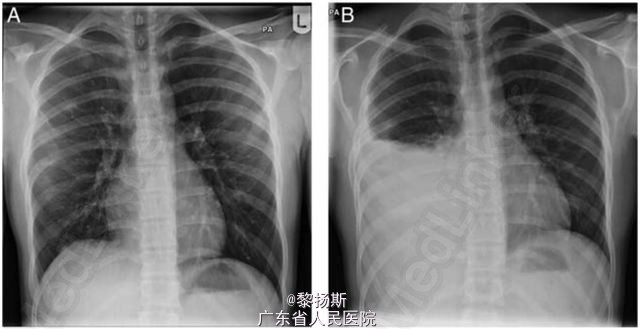

14 岁男孩,因右侧胸痛、咳嗽伴间歇性发热 2 周到我院儿科急诊就诊。胸片所见如(图 1A),就诊后嘱托患者若症状无缓解则需再次返院就诊。1 周后患者再次就诊,呼吸费力、胸痛、体温最高达 38.5℃。

体查检查发现右侧胸部叩诊浊音,呼吸音减弱。复查胸片结果见图 1B。 首次就诊血液学检查白细胞计数正常,C 反应蛋白升高(303 mg/L)。患儿呼吸急促,需要吸氧 1-2L/min,同时对患者静脉用克拉维酸和克拉霉素。胸部超声证实存在大量胸腔积液,疑诊脓胸,遂转入我科进一步治疗。